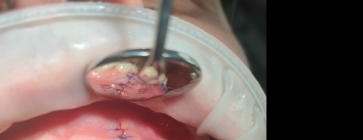

Rozległa torbiel zawiązkowa żuchwy

Paulina Adamska, Maria Mikołajska, Anna Janowska, Anna Starzyńska